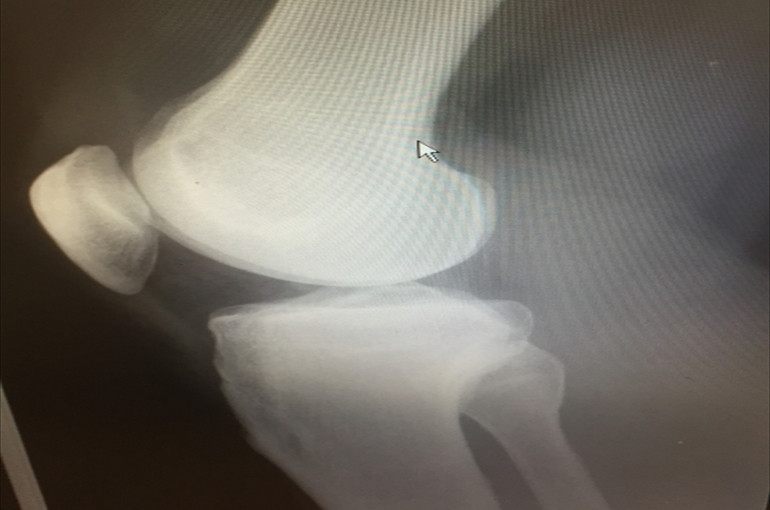

膝のお皿(正面)付近が痛む理由の

2つめは膝の関節液の低下です。

そもそも関節液とは何か?

膝のお皿の内部には

関節液と呼ばれる液体状の

物質があり、

これが潤滑油の役割をしているので

骨と骨がスムーズに動いたり、

緩衝材の役割も果たしたりします。

しかし、この関節液がないと

骨がスムーズに動かなかったり、

直接ぶつかったりして

痛みが生じます。

関節液はヒアルロン酸や

たんぱく質等が構成されています。

よく膝にヒアルロン酸注射を

するのはこのためです。

加齢と共に体内が作る

関節液の量も減ってきて

痛みが生じやすくなります。